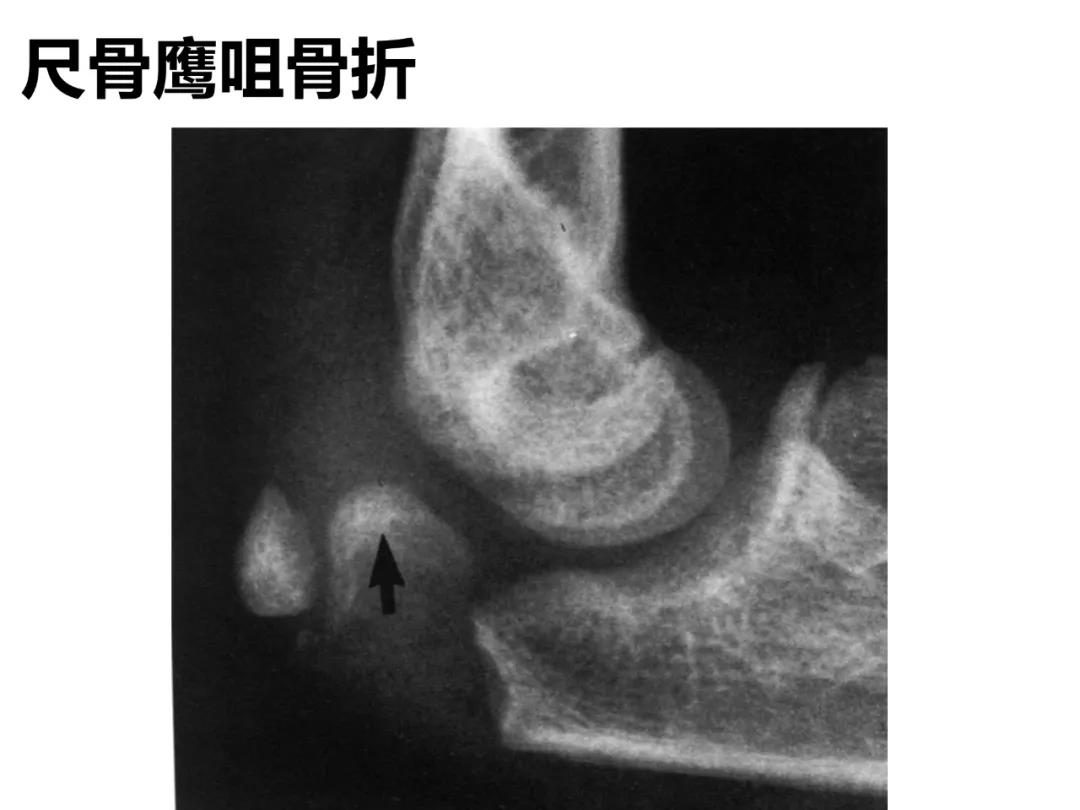

小儿骨科X线片汇总,临床读片宝典!